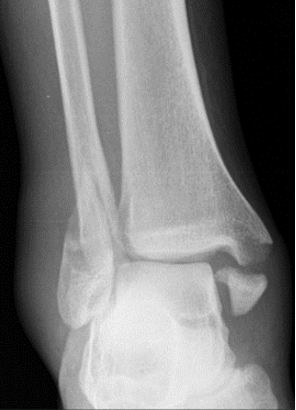

What type of fracture is this?

Pott

What is a pott fracture?

Complete fracture of distal fibula, may involve ligament damage and fracture of medial malleolus and distal tibia